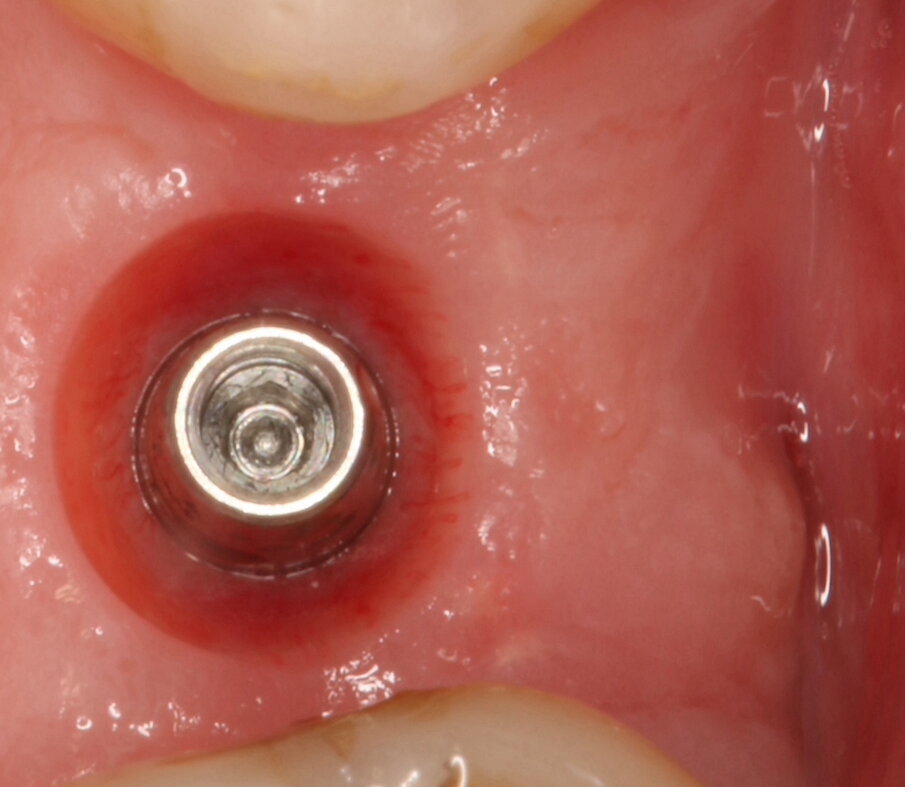

Fig. 5_Applicazione del moncone conometrico dritto.

Fig. 8_Guarigione dopo 4 mesi.

Fig. 9_Guarigione dopo 4 mesi con focus sui tessuti molli perimplantari.